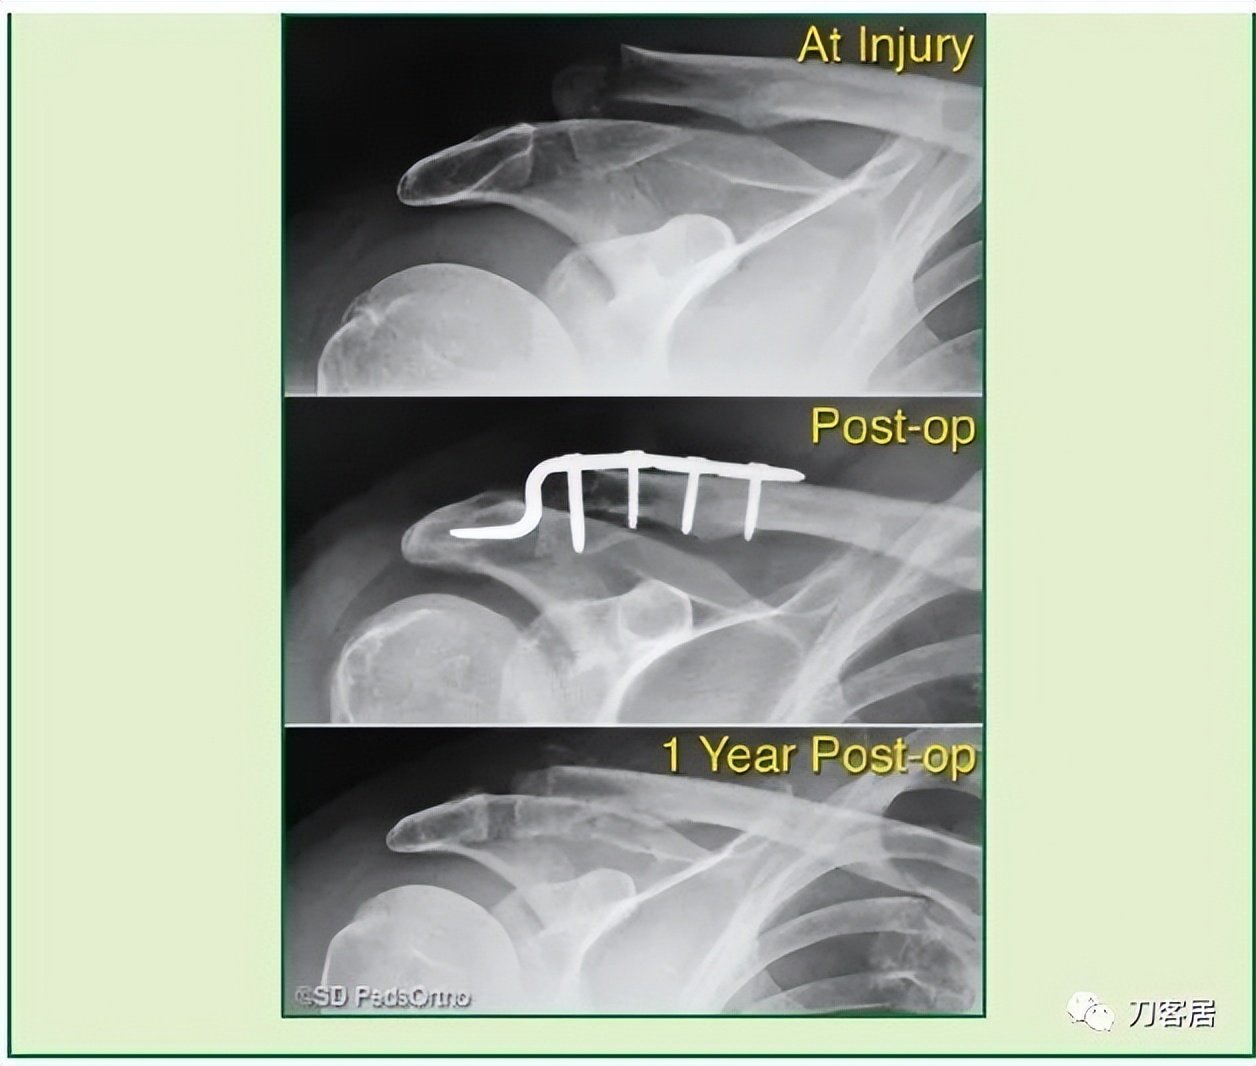

When surgical fixation is potentially required (Type IV, V, or VI injuries), controversy exists as to the optimal fixation technique with some favoring Kirschner wires, others hook plates, pre-contoured lateral clavicle plates, coracoclavicular fixation devices, or a combination thereof (Table 6-3). In the rare circumstance where pin fixation is used, we advocate significantly bending the pin outside the skin to minimize wire migration and weekly clinical evaluations until the pins have been removed (typically 3-4 weeks). The literature indicates that there can be significant complications from pin migration, including death. We believe each of these cases must be approached on an individual basis based on the size and comminution of the fracture fragments.

当需要手术固定时(IV、V或VI型骨折),采取何种固定技术存在争议,有人喜欢用克氏针,另有人喜欢钩板、预弯外侧锁骨板、喙锁固定装置或它们的组合(表 6-3)。在罕有的髓内针固定时,我们主张将针的一端折弯留置皮肤外侧,以防固定针移位,并且每周随访直至固定针去除(一般需要 3-4 周)。文献表明,固定针移位可能会导致严重的并发症,甚至死亡。我们认为,每个病例都应该根据骨折粉碎程度以及骨折块的大小,遵循个体化治疗原则,决定治疗方案。